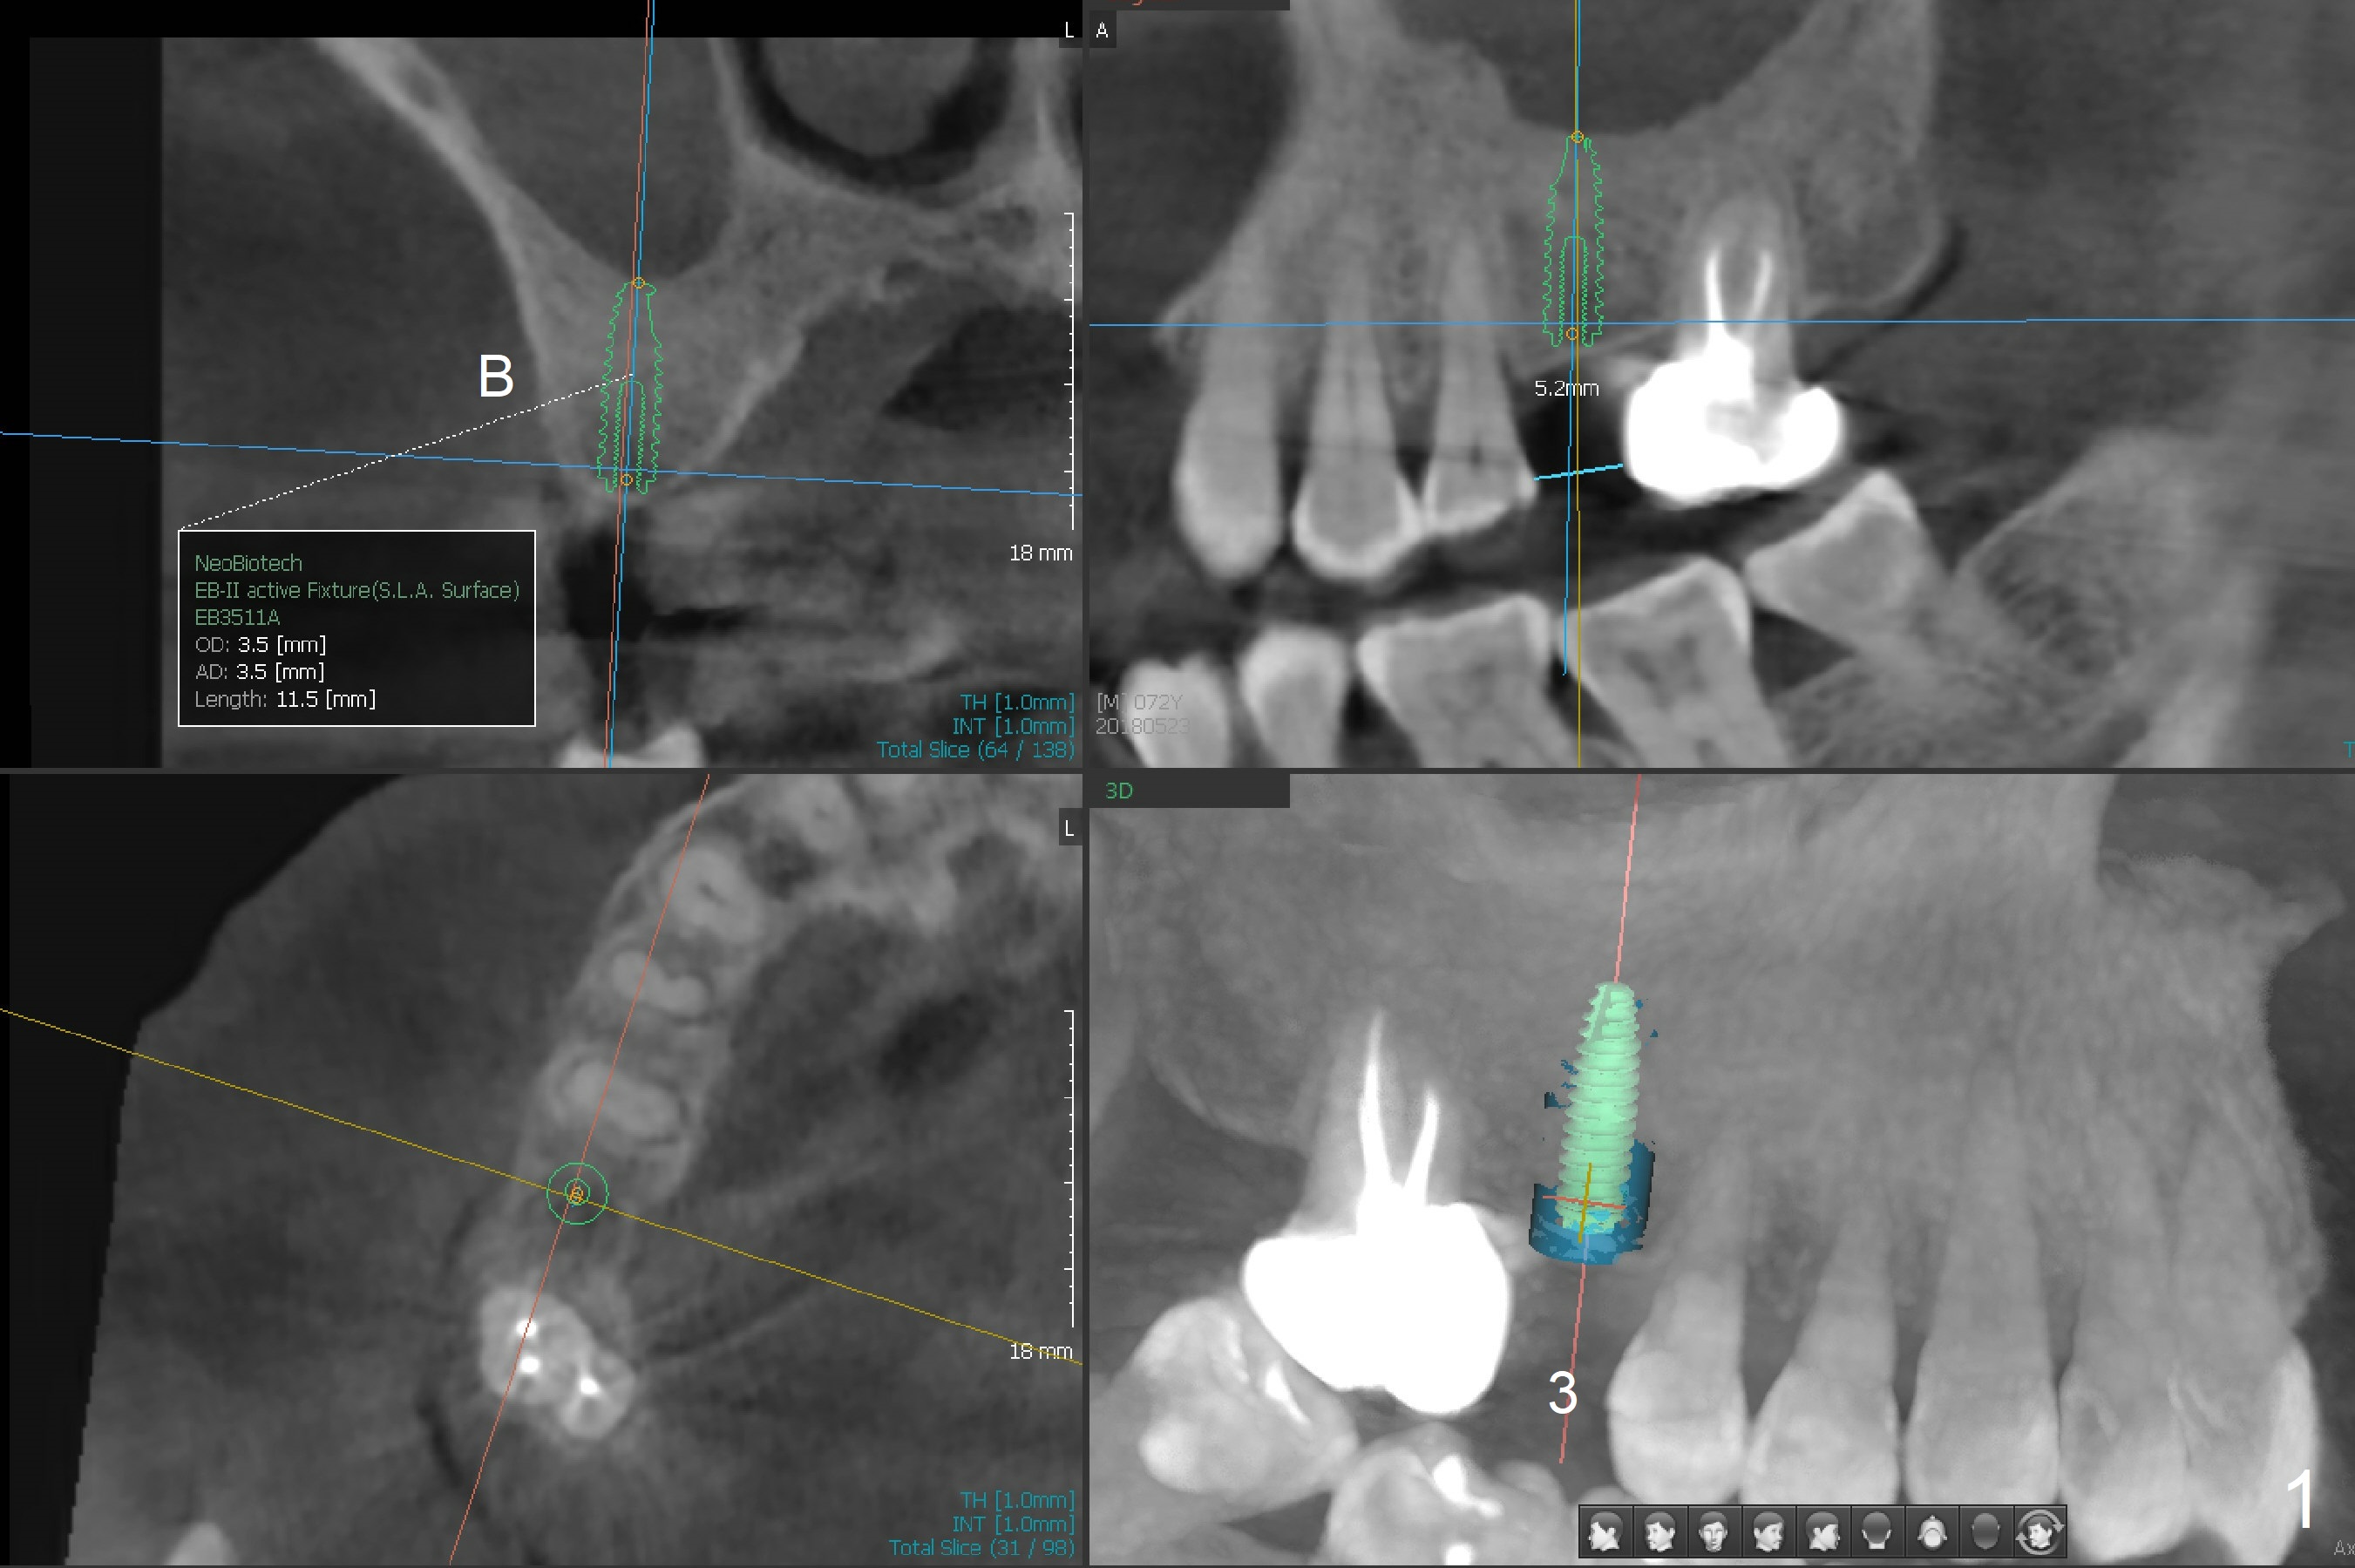

I have reviewed the patient's #3 position and as you have also indicated, interproximal distance is 5mm so regular metal sleeve won't fit in. So narrow metal sleeve with yellow color should be used. The best implant size would be 4.5 X 10.0mm but in order to use narrow sleeve with some offset, 3.5 X 10.0mm implant placement is suggested.

So, that's why I suggested 4.5mm diameter first on the screenshots. But for this case, due to narrow space only diameter that will work would be 3.5mm diameter. sizewise.

If the patient agrees, I would like you to make a guide so that a 3.5x10 mm 1-piece implant will be placed.  Thanks.